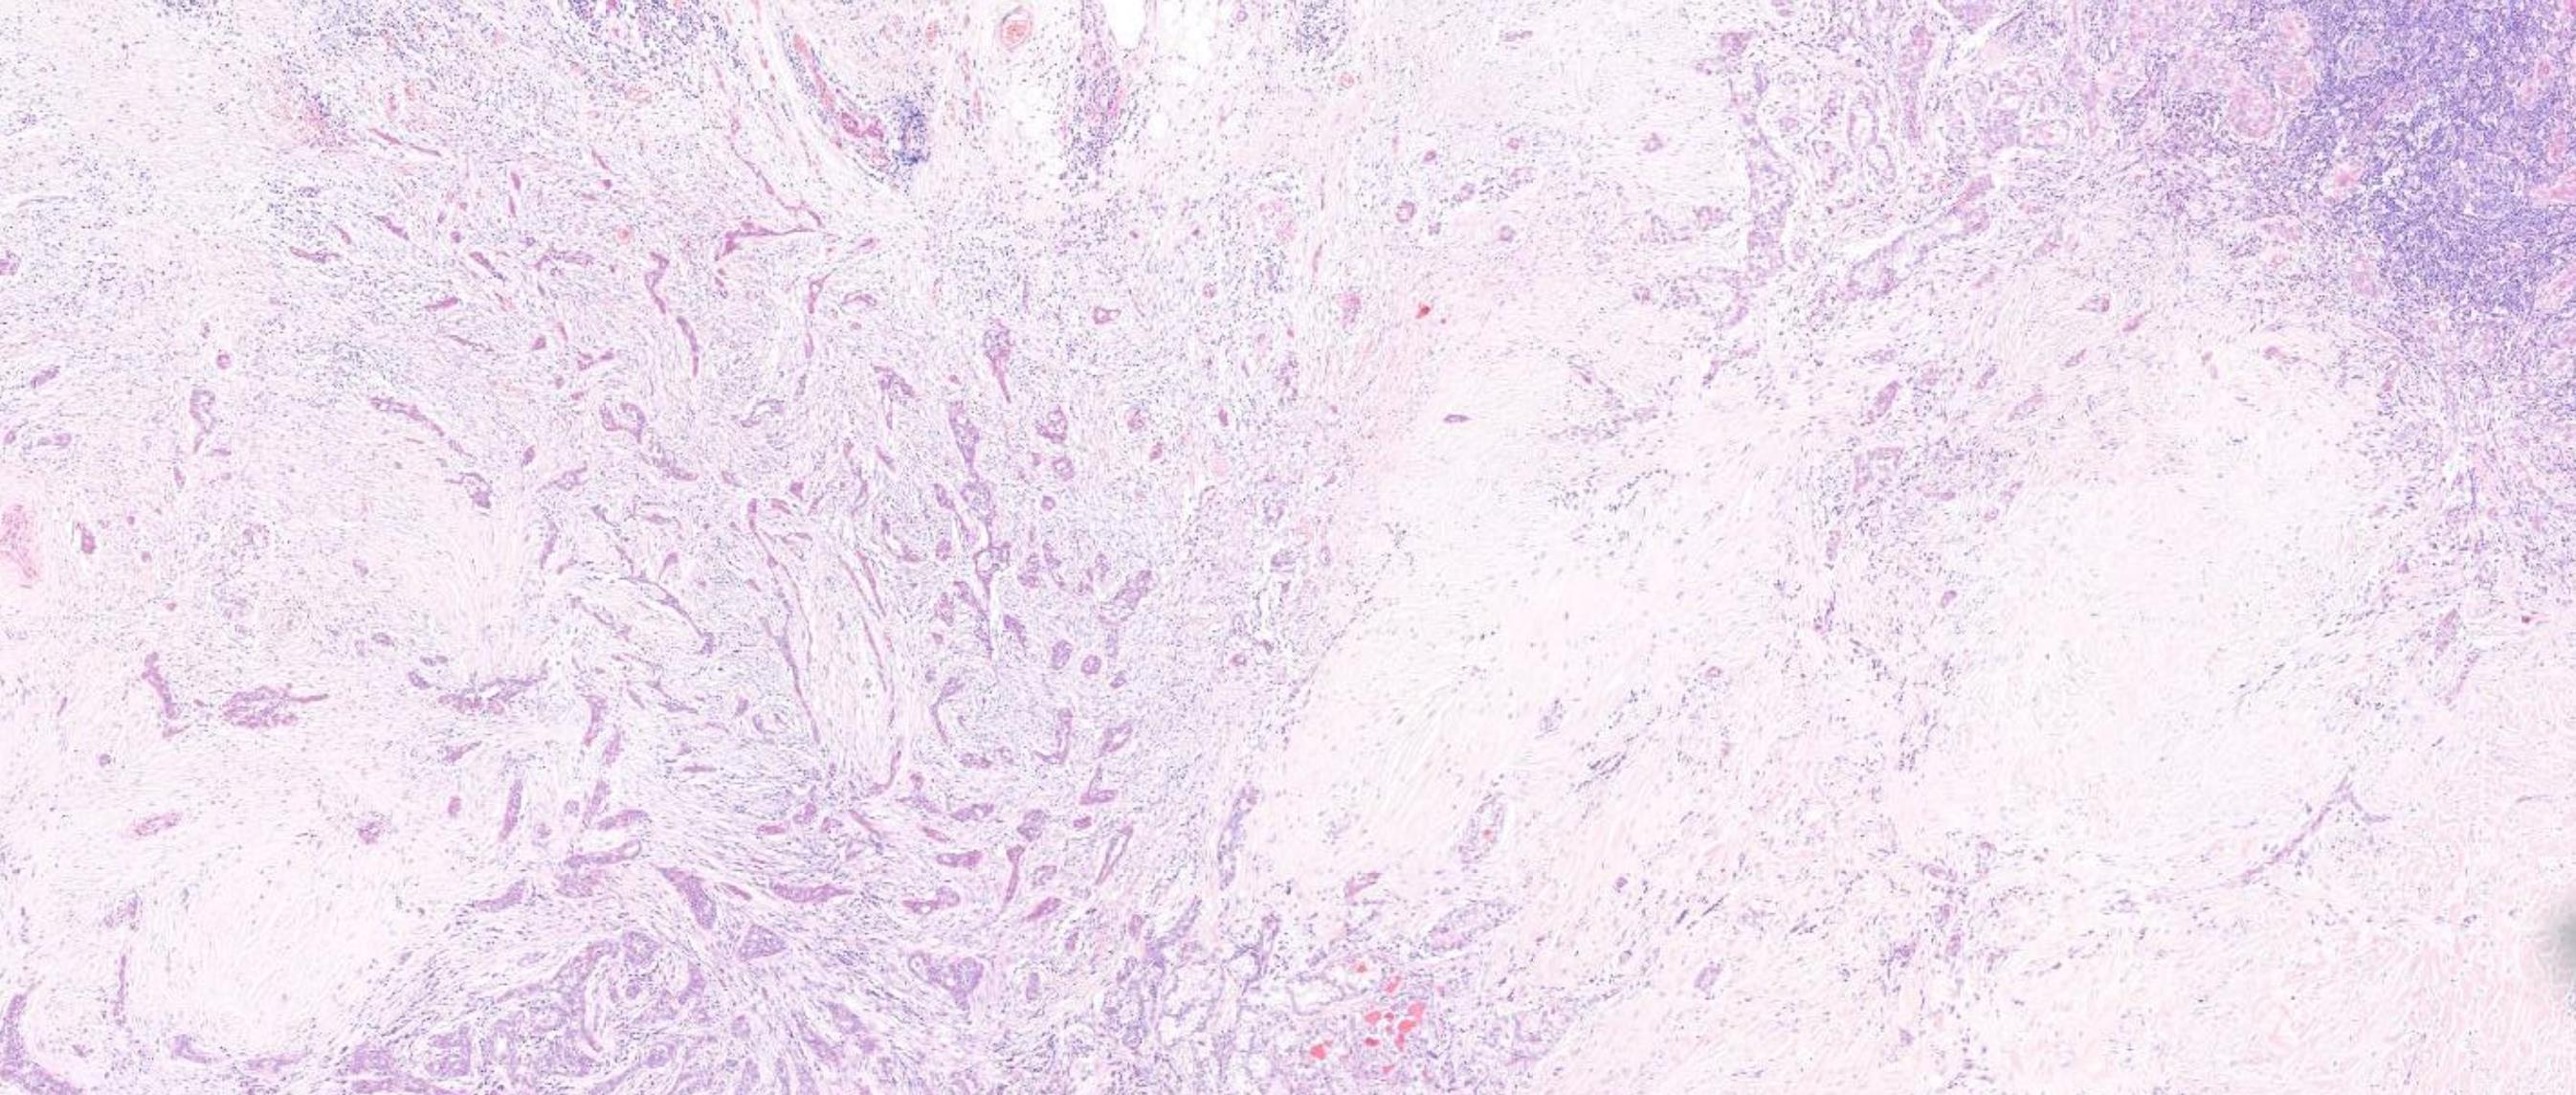

42-year-old Female, Left level 4 lymph node.

Case 4 Diagnosis

Metastatic diffuse sclerosing variant of papillary thyroid carcinoma

Diffuse enlargement, Solid tumour nests with squamous metaplasia, including squamous morules, dense sclerosis, numerous psammoma bodies, background chronic lymphocytic thyroiditis This tumour is common in children and young adults BRAF mutation (50%), RET/PTC1 rearrangement (28%), RET/PTC3 (14%) Highlights